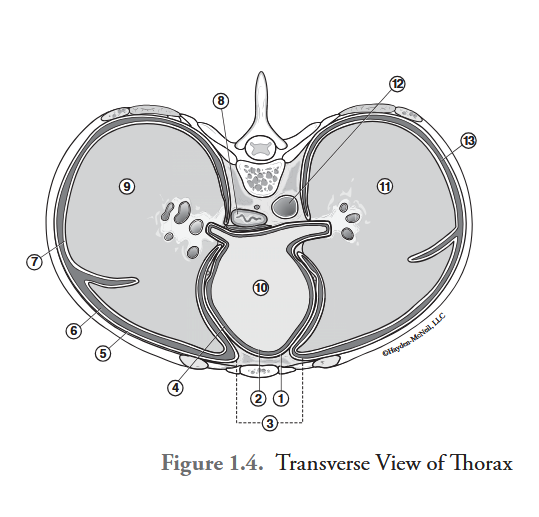

What is labeled #1?

parietal pericardium

What is labeled #2?

visceral pericardium (epicardium)

What is labeled #3?

mediastinum

What is labeled #4?

pericardial cavity

What is labeled #5?

parietal pleura

What is labeled #6?

right pleural cavity

What is labeled #7?

visceral pleura

What is labeled #8?

esophagus

What is labeled #9?

right lung

What is labeled #10?

heart

What is labeled #11?

left lung

What is labeled #12?

descending aorta

What is labeled #13?

left pleural cavity